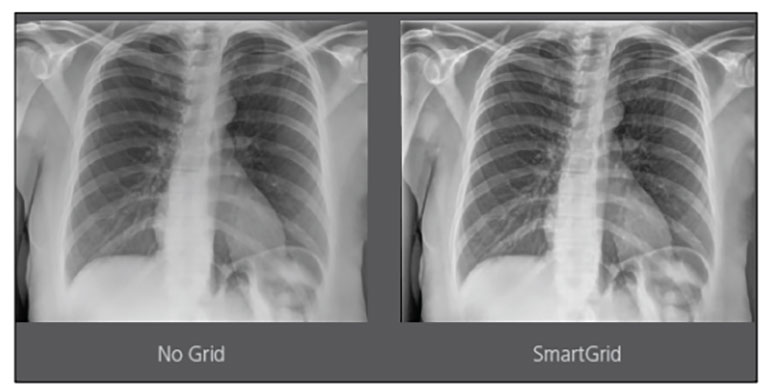

CARESTREAM Image Suite V4 MR11 has set a new standard for workflow efficiency, offering a robust set of features and functionalities to enhance clinical confidence in healthcare professionals. Using an auto-generated companion image from a single exposure, leverage a range of image processing options to increase diagnostic accuracy and enhance patient care.

By Praveen Rajgopal, Global Product Marketing Manager

Upgrading your imaging system to a solution designed for outstanding image quality is no longer out of reach — it's now easier, more affordable, and more effective than ever before.

Our Carestream Focus HD 35/43 Retrofit Detectors, powered by Image Suite Software, are an ideal solution to step up to full digital X-ray for customers who simply cannot compromise on image quality. It seamlessly integrates into existing setups, bringing the power of full digital X-ray with minimal disruption and maximum clarity, along with the following benefits: